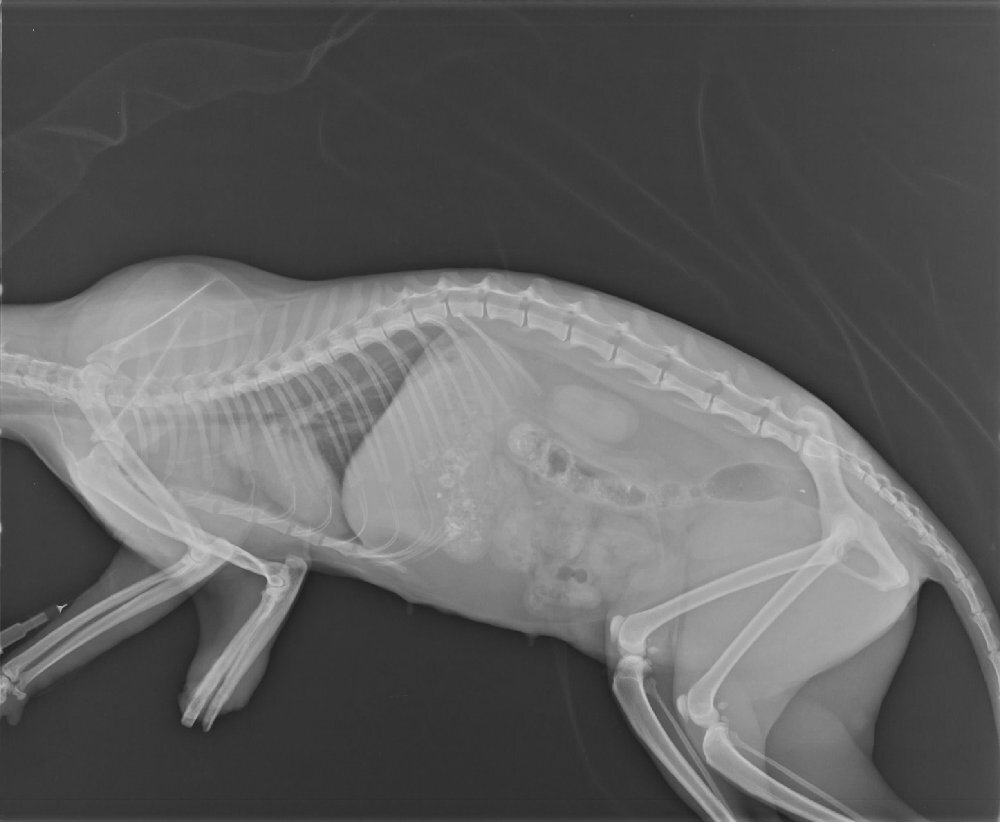

- 編號: 2980

主題: 撫遠街三腳三花貓救援 申請者姓名: 臺北市支持流浪貓絕育計劃協會 花色: 申請日期: 2013-09-12 16:05:09 申請者部落格: 申請者臉書網址: https://www.facebook.com/SupportTNR 所在縣市/合作醫院: 台北市/極光動物醫院 治療費用: 27585元 需求人數: 29人 已結案 (2014-01-10 18:00:19) 報名人員: Js Lee(已付款)、irame65 x2(已付款)、駱xx(已付款)、Usay Huang、陳小茜(已付款)、Usay Huang、蔡秀芳、Sheirly Chu(已付款)、Kiki Liang(已付款)、林韋韋(已付款)、麵貓匪(已付款)、vivian、Wendy x2(已付款)、Stephen(已付款)、Gina Pan(已付款)、有貓真好(已付款)、邱小鯊(已付款)、Sherry Fang x2(已付款)、Emily Chou x3(已付款)、Edmund_Chang(已付款)、jenny(已付款)、李子均(已付款)、Kuen-Lin Tsai(已付款)、Ou Han(已付款)、Fg Jan(已付款)、Jau Shiang Hsieh(已付款)、劉蔓蒂、黃瓊瑩(已付款)、Debbie Lin、miraai(已付款)、 候補人員: 動物病情說明: 於撫遠街,松山機場盡頭社區被發現的三腳貓,左前肢疑似被捕獸夾夾斷,露出白骨,志工先後前去尋找,在廟旁的一處空地發現,誘捕送醫截肢,並做絕育手術,因附近有不少浪狗,三腳貓在野外,生存不易,出院後先安置於協會。 動物近況說明: 目前安置於協會安養之家,視情況看是否可以安排送養。